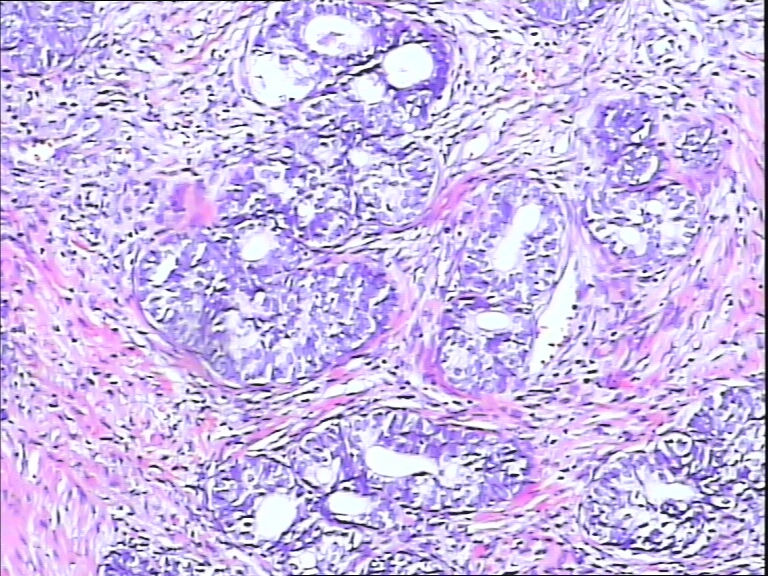

前列腺,请教,急!

图4

前列腺够癌吗?